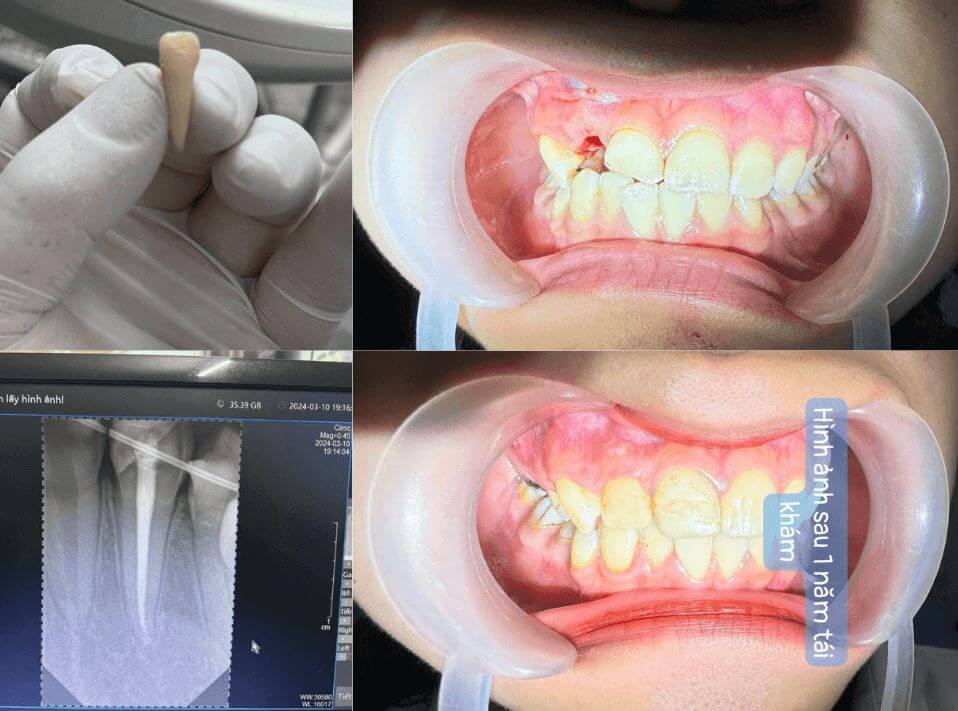

“Cách đây hơn một năm, em bị tai nạn ngã xe, răng cửa số 2 gãy ngang và lung lay rất mạnh. Cứ nghĩ chắc phải nhổ bỏ hoàn toàn rồi làm răng giả, em vừa sợ đau vừa lo mất thẩm mỹ vì răng cửa rất quan trọng.

May mắn em được người quen giới thiệu tới Thiên Đức, bác sĩ kiểm tra kỹ, chụp phim và quyết định nhổ phần thân gãy ra, phục hồi phần còn lại, sau đó cắm lại vào huyệt răng cũ và cố định luôn. Nghe thì lạ nhưng nhờ tay nghề bác sĩ tốt và chăm sóc kỹ đã phục hồi được răng cho em.

Hôm vừa rồi em đi tái khám sau 1 năm, răng không những giữ được mà còn chắc chắn, hồng hào như bình thường. Em thật sự biết ơn bác sĩ và các cô chú y tá tận tình chăm sóc!”

– Nguyễn Thị H., 20 tuổi